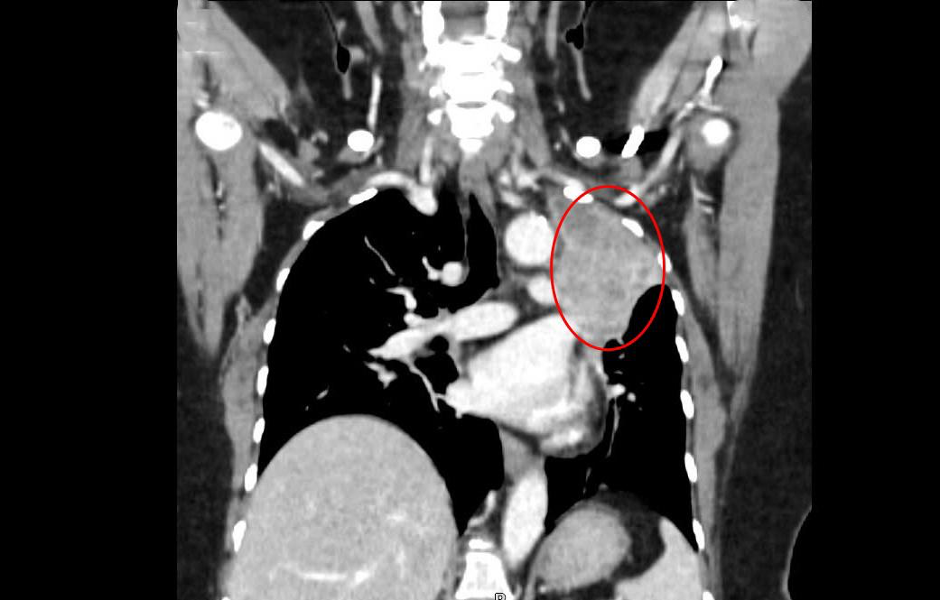

Doctor Nguyen Tran Anh Thu, from the Oncology Department, Oncology Center, stated that brain tumors can cause symptoms similar to a stroke, leading to patient confusion. These tumors are highly likely to be metastatic cancer. The doctor ordered a CT scan of the upper lobe of the left lung, which showed a lesion over 7 cm with irregular borders, causing surrounding lung collapse.

The CT scan results showed Ms. Hoa's left lung had a tumor over 7 cm. *Photo: Tam Anh General Hospital*